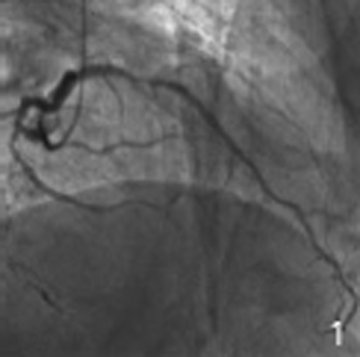

左主干分叉病变

西京医院术者:李伟杰 郭文怡 王海昌病例描述:即往病史:高血压20年术前血管造影情况:冠心病 急性NSTEMI手术过程:1.使用7

• 左主干

左主干

西京医院术者:王海昌 李伟杰病例描述:即往病史:入院诊断:冠心病 不稳定性心绞痛 陈旧性前壁心肌梗死术前血管造影情况:RCA2-3